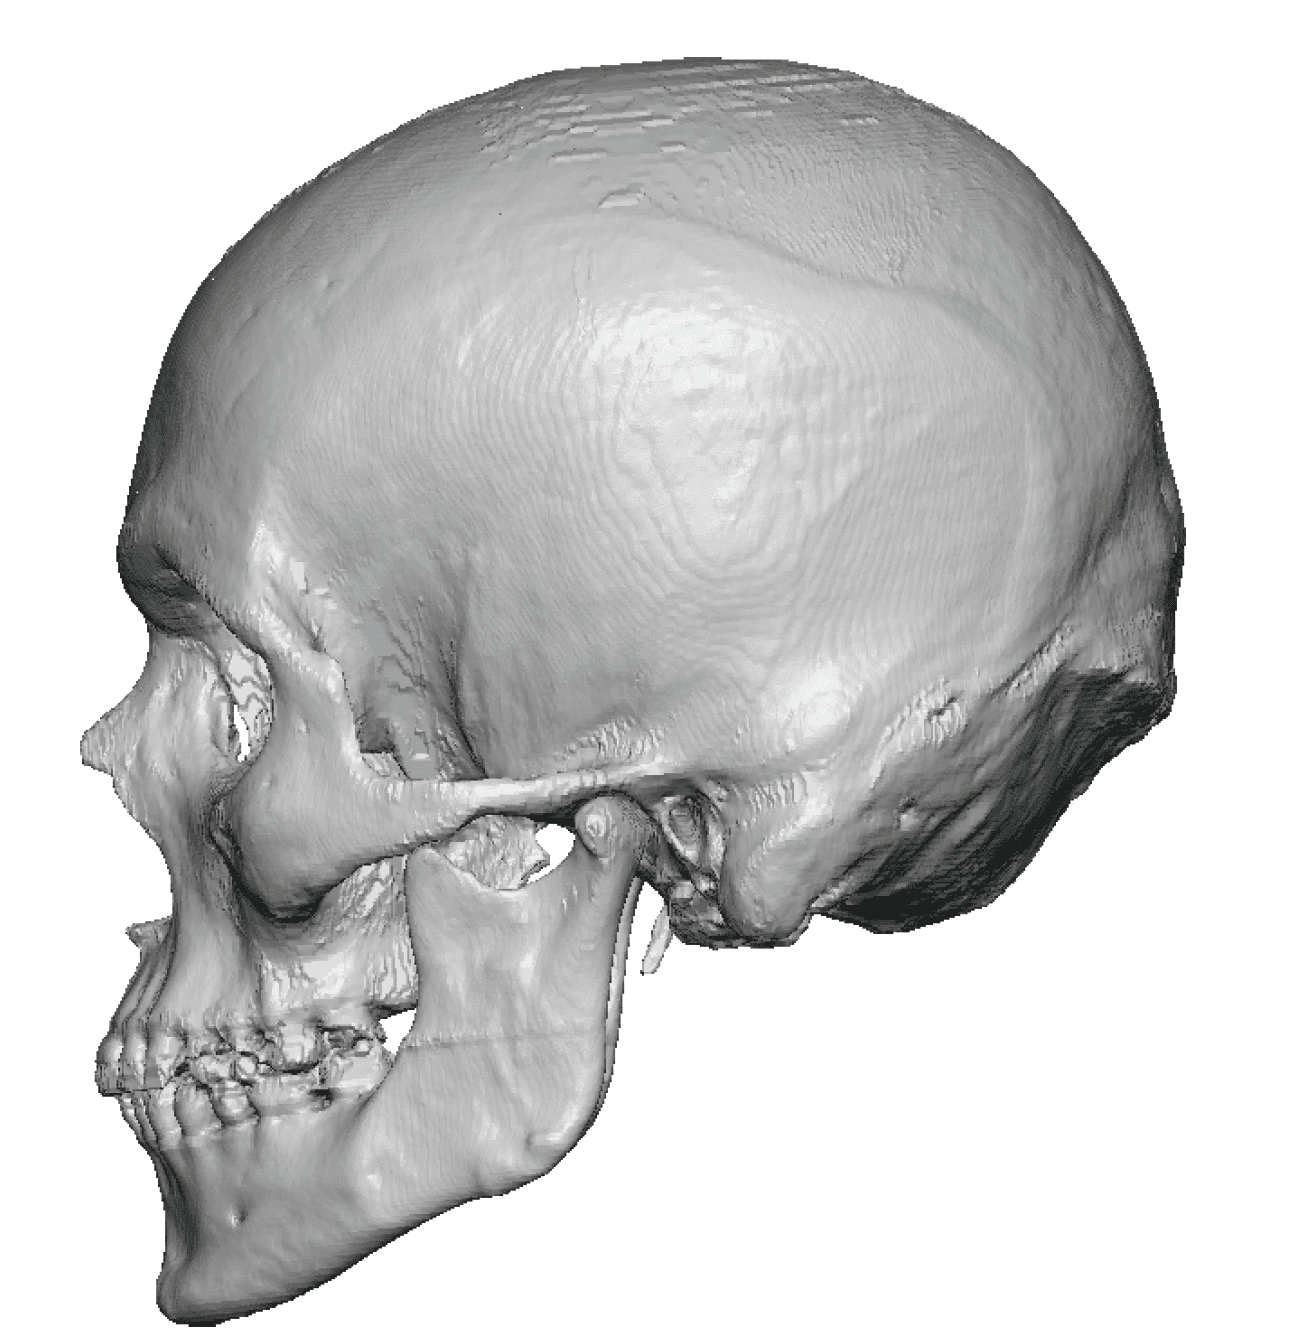

Patient 100

Desire for reshaping of an asymmetric flat back of the head in a shaved head male.

A combined back of the head reshaping procedure was done with a custom skull implant, sagittal ridge reduction and a right temporal muscle reduction.

Desire for reshaping of an asymmetric flat back of the head in a shaved head male.

A combined back of the head reshaping procedure was done with a custom skull implant, sagittal ridge reduction and a right temporal muscle reduction.